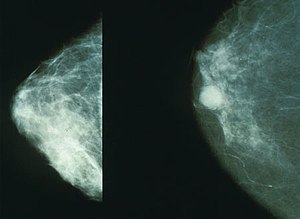

유방암 2기는 암세포가 유방 내에 머물러 있지 않고, 주변 림프절까지 퍼졌지만 다른 장기로 전이되지는 않은 상태를 의미합니다. 이는 비교적 조기 발견에 속하는 단계로, 적절한 치료를 통해 완치 가능성이 높은 편입니다. 다만, 유방암 1기와 비교해 생존율에 차이가 존재하기 때문에 환자와 의료진 모두 더 세심한 관리가 요구됩니다.

유방암 2기의 5년 생존율은 대체로 70%에서 90% 사이로 보고되고 있습니다. 이는 초기 유방암 단계에 속하지만, 암의 크기와 림프절 전이 여부에 따라 생존율에 차이가 생깁니다. 일반적으로 림프절 전이가 없을 경우 생존율이 더 높으며, 전이가 있는 경우라도 조기 치료를 통해 상당한 생존율 향상을 기대할 수 있습니다.